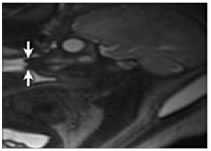

Figure 2: A, Sonogram of a fetus with maxillomandibular fusion showing lack of a normal gap between the mandible (arrow) and maxilla (arrowheads). Also note the small chin and protuberant lips in comparison with B and C. B and C, Sonograms of unaffected fetuses of the same gestational age with closed mouths. Note the substantial gap between the mandible (arrows) and maxilla (arrowheads) in both cases compared with A. Figure 3: The fetal MRI showing a small chin, a characteristically protruding jaw, and prominent, protruding lips Figure 4: Postnatal CT of the affected neonate. A, Postnatal off midline sagittal head CT showing fusion (black arrow) of the mandible (white arrow) and maxilla (arrowhead). Fusion was seen on multiple slices, more easily visualized on the 3D CT reconstruction (B). B, Postnatal 3D CT reconstruction of facial bones. Sagittal view depicts fusion of the maxilla and the mandible. The fusion in this case involved bilateral bony fusion of the mandibular and maxillary alveolar processes, with a small anterior slit remaining. The fusion also included fusion of the proximal parts of the mandibles, the ascending rami, to the posterior portions of the maxillas and to the zygomas bilaterally. However, the ascending rami of the mandibles were not fused to the zygomatic processes (asterisk) on either side. The coronoid processes of the mandible (arrowhead) are visualized, pointing to the most proximal aspect of the mandible. T indicates temporal bone; and Z, zygomatic bone. The dotted line represents the expected area of separation between the mandible and the maxilla. DISCUSSION Maxillomandibular fusion has always been an unanticipated diagnosis made at birth. Given that congenital oral cavity deformities have potential for causing difficult airway and respiratory impairment, prenatal diagnosis would allow appropriate preparation of staff for airway management at the time of delivery. Given the advanced imaging techniques available today, such as real-time sonography and fast sequences for fetal MRI, maxillomandibular fusion can potentially be detected prenatally.6 The reported sonographic findings in a case of maxillomandibular fusion, were an absence of mouth opening and a contiguous appearance of the upper and lower jaws. In normal fetus, there is normally a gap between the maxilla and mandible on sonography. Various studies have reported real-time sonography as a reliable method for the evaluation of fetal movement, particularly fetal facial expressions, in the second and third trimesters.8 These studies reported mouth opening in the context of swallowing, suckling, chewing, and even yawning detected by real-time sonography in fetuses without abnormalities. According to these studies, continued observation by real-time sonography (for anywhere between 15 minutes and 2 hours, depending on the study) is a reliable and reproducible method for visualizing fetal mouth opening. One of the studies even reported regular mouth openings during fetal quiet and active sleep states.9 Because fetuses with maxillomandibular fusion are incapable of opening their mouths, real-time sonography can a definite method of excluding this rare disorder in suspected cases. Real-time sonography would be best performed during the second trimester for optimal visualization of the fetus. 3D and 4-dimensional (4D) sonography can also be valuable in suggesting or diagnosing maxillomandibular fusion prenatally. Numerous recently published articles emphasized that the interpretation of the fetal image, especially of the fetal face, is easier and faster with 3D images than with 2-dimensional (2D) images.10,11 Three dimensional sonography has the capability of showing planes of a section that cannot be obtained with 2D sonography and thus allows for a comprehensive evaluation of facial anatomy. Kurjak et al11 commented on the specific advantages of the assessment of the maxilla and mandible for the diagnosis of micrognathia and retrognathia. Surface-mode rendering, in which the surface within the volume of interest (generally the skin) can be seen without the underlying tissue, has proven very useful in the evaluation of facial abnormalities.10 In the case presented here, the facial characteristics visualized on the The fetal MRI shows the maxillary and mandibular tooth buds to be closely apposed without the intervening space seen in unaffected fetuses. MRI revealed an open mouth on most sequences in all fetuses without maxillomandibular fusion.5,6 MRI would likely have been identified on 3D sonography if performed during the second trimester. The maximum-rendering mode highlights the maximal echo (bone) information of a volume data set and is an ideal tool for the 3D reconstruction of bony structures. Generally, cranial bones, the ribs, and other curvilinear bones, which cannot be properly visualized in a single 2D plane, are better assessed in a maximum- mode projection.11 Selectively imaging the bones on sonography can undoubtedly add to the potential of sonography for suggesting or diagnosing bony maxillomandibular fusion. Finally, 4D sonography, by adding the temporal component (as a virtually live 3D image) in the surface-rendered mode, has been described as advantageous in accurate visualization of subtle and fast facial expressions.11 The use of 4D sonography to monitor small or fast jaw and mouth movements (complementary to real-time conventional 2D sonography) would also be of potential value in the evaluation of suspected cases of maxillomandibular fusion. Both the management and outcome of patients with bony maxillomandibular fusion have varied. The rarity of the condition makes standardization of treatment difficult.